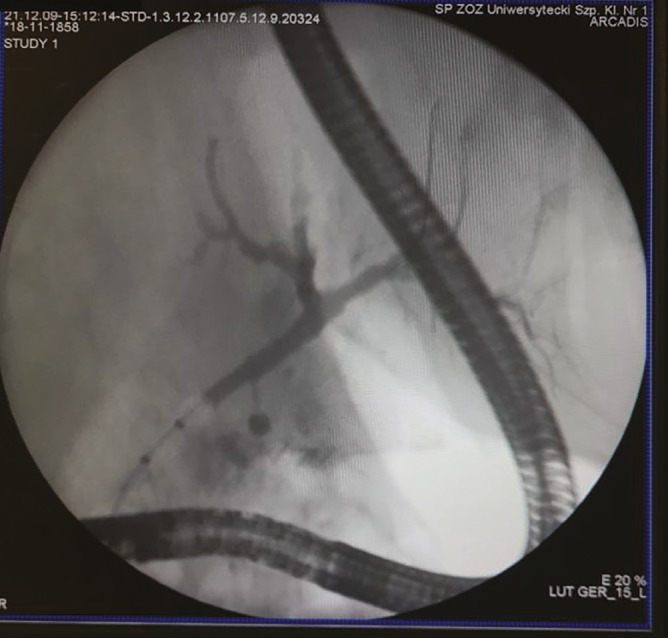

Abstract Image